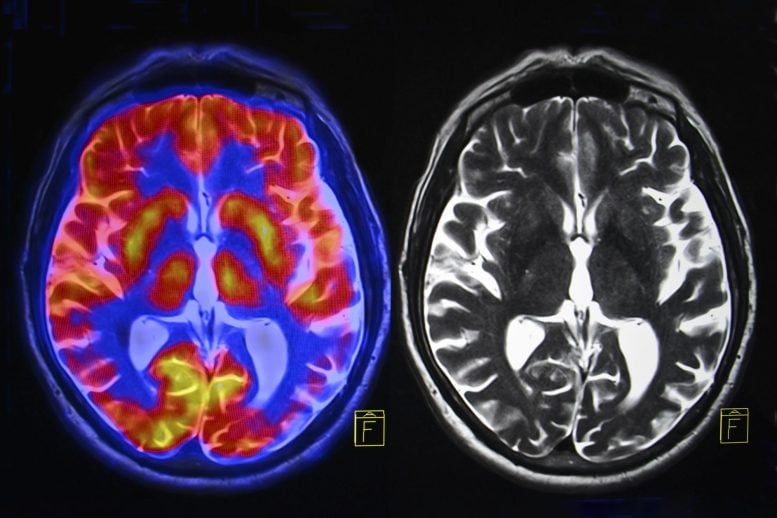

A newly identified brain network may be the real driver of Parkinson’s—and precisely targeting it just delivered a major boost in symptom relief. Parkinson’s disease is a progressive neurological condition that affects more than 1 million people in the United States and over 10 million worldwide. It causes a wide range of disabling symptoms, including […]Health,Brain,Neurology,Parkinson’s Disease,Washington University in St. Louis,Washington University School of Medicine#Scientists #True #Source #Parkinsons #Disease1770222765